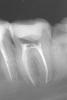

natalia sado Опубликовано 3 ноября, 2012 Поделиться Опубликовано 3 ноября, 2012 Здравствуйте. Моя ситуация такова: зуб 37 был пролечен летом, нерв не трогали, поставили пломбу. Но! впоследствии появилась боль при накусывании (т.е. жить мне он не мешал, болеутоляющие я не пила, но понимала, что корочку хлеба он жевать не может. Иду к врачу, говорит: "я знал, потому как пульпа была слишком близко, пожалел тебя и зуб, а надо было депульпировать" Что он и сделал. (см снимки 1 и 2). Также он решил, что нужен штифт, но это позже, нужно чтобы прошло время. Время это как раз нам было очень на руку, потому как сразу от него я пошла в кабинет хирурга удалять соседнюю восьмерку,от которой накакуне просто отвалился кусок. Я еще помню подумала, что может оно как-то не очень сочетать эндодонтическое лечение и удаление соседнего зуба, тем более что зуб мудрости был ого-го!! а удалял мне его хирург 1.5 часа (врач кстати отличный), но возможно это всего лишь женская привычка все преувеличить Пошла я восвояси заживлять лунку, с временной пломбой на 37 зубе, ожидающего штифта и реставрации. Дело было 9 сентября.В 20х числах сентября я была на осмотре у хирурга, т.к. восьмерка у меня заживать не хотела, промучилась я с осложнениями, но не так все просто - опять напасть: За это время замечала снова болевые ощущения на этой 7ке, пробовала пожевать, когда лунка позволила-те же симптомы, все точно также, опять на грубую пищу такая реакция (надо сказать, что эта симптоматика вообще стала мне родной за последнее время, это был не первый зуб со схожими проблемами). Тут же заруливаю к своему лечащему. Сделали снимок (3), посовещался с коллегами- все в один голос: неееееет!!! не может быть!! чему тут болеть, запломбировано все идеально, это оседает материал. ну ок! только вот неделю назад надоело мне ждать, пока "он осест" и я пошла с твердым намерением сделать снимок (кстати действительно настояла, опять пытались переубедить).И вот результат: фото 4! даже я вижу, с каналами то проблема!! уже и мой врач не отрицает , но хотелось бы понять, судя по динамике снимков, что же произошло, почему, и что тут теперь вытворять?Пожалуйста, выскажитесь, очень важны ваши советы и мнения. Уже обращалась к вам недавно по поводу синуслифта, помогли настроиться и принять решение. Очень не хочется вслепую вершить судьбу своих зубов. Ссылка на комментарий

natalia sado Опубликовано 3 ноября, 2012 Автор Поделиться Опубликовано 3 ноября, 2012 Вот только фото разместились четко наоборот))Чтобы соблюсти хронологию снимков, отсчет по номерам, кот. я указала в тексте, ведем справа налево Ссылка на комментарий

Magdalena Опубликовано 3 ноября, 2012 Поделиться Опубликовано 3 ноября, 2012 За период от первого до последнего снимка на корнях появилось воспаление. Причины могут быть 1. Погрешности в обработке каналов, лечение без изоляции зуба коффердамом ( могла слюна попасть с микробами) 2..Впечатление, что на снимке с инструментами в дистальном корне (ближе к 8 зубу) есть еще один канал. Уточнить до перелечивания можно сделав 3д-томограмму. Ссылка на комментарий

DmitrySH Опубликовано 11 ноября, 2012 Поделиться Опубликовано 11 ноября, 2012 Проблема в том, что на снимке признаки воспаления есть двух корнях. А в каждом корне по 2 канала. Соответственно переделывать нужно все. Ссылка на комментарий

ger_berra Опубликовано 12 ноября, 2012 Поделиться Опубликовано 12 ноября, 2012 Я вижу в Вашем зубе апикальную перфорацию.Это ложный ход корневого канала,который делается инструментом .Не нарочно,конечно.Таким образом в очень важной части канала("верхушка") осталась органическая ткань("нерв"),к которой присоединились микроорганизмы из слюны,которые её кушают.Обработка проводилась без коффердама,так что запросто могло "натечь в зуб".Если зуб дорог,то его нужно полностью "перебрать",отмыть,с временной пломбировкой гидроксидом кальция и плотной постоянной пломбировкой. 1 Ссылка на комментарий